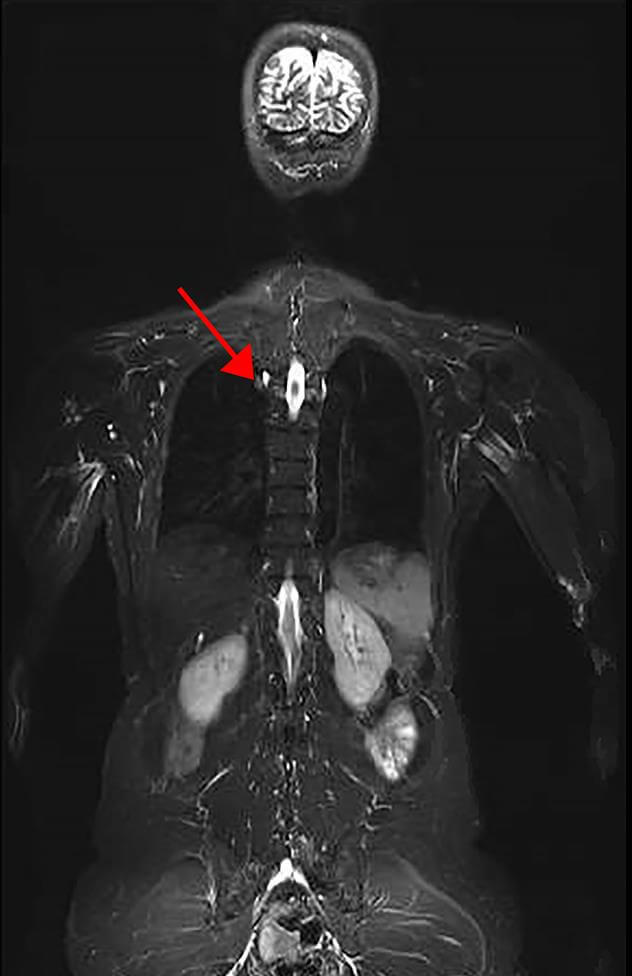

Part of a representative image of a whole body MRI of an LFS patient. Arrow denotes lesion found to be lung adenocarcinoma.

To address this gap in clinical care, researchers modified a cancer surveillance protocol from a previously published study and screened 116 LFS patients with germline TP53 mutations using a variety of tools including whole body, brain, and breast MRI, as well as mammography, colonoscopy, bloodwork, and abdominal ultrasound. The study used modalities that do not utilize ionizing radiation for imaging (except mammography), since patients with LFS appear to be radiosensitive.

They found that 40 trial participants (34 percent) had abnormalities on baseline screening examination with whole body, brain, or breast MRI that required further evaluation. Eight of these patients (7 percent) were diagnosed with a new primary cancer. All but one of the cancers found through screening were fully removed with surgery. In contrast, the non-MRI techniques used in the trial did not lead to a diagnosis of cancer at baseline screening.